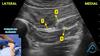

Essa janela é de um bloqueio de membro inferior para cirurgia no tornozelo. O que são as estruturas em destaque?

A

1 - artéria poplíta;

2 - nervo tibial;

3 - veia poplítea

Esse é o bloqueio do nervo ciático na fossa poplítea.